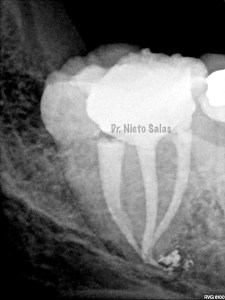

Así pues quedaría el sellado hermético y tridimensional:

La otra pieza, el 3.7, se instrumentó con sistema Protaper y obturación con Ola continua de Calor y un back-filling con la pistola Obtura II.

2. disculpe, en las imagenes de la entrada de los conductos, era dos conductos distales o era solo uno ?? muchas gracias y enhorabuena por el casa, es perfecto !!

3. Dr Nieto Salas, en la imagen en que se ven la camara con la entrada de los conductos y la gutapercha, el orificio de entrada en distal era muy ancho, a parte de conductos laterales, localizo un conducto o dos conductos ?? ( la duda es por lo ancho de la entrada). El caso es maravilloso. Le doy mi enhorabuena.

4. Hola Juan,

en ese caso en particular, el número de conductos era solamente uno, ya sabes que los conducto distales en muchas ocasiones tienen forma ovalada, con lo que la entrada puede corresponder con las imágenes.